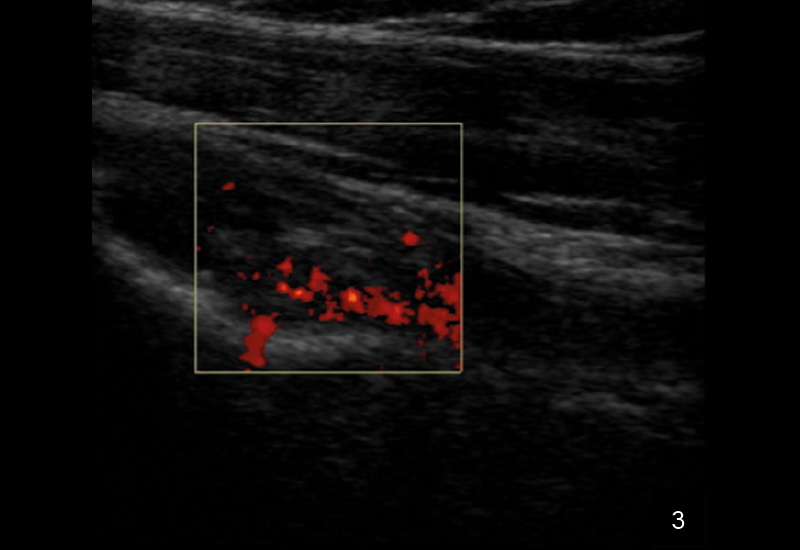

Die Sonografie gilt als erstes bildgebendes Verfahren hoher Wertigkeit bei der Diagnose einer Tenosynovitis der langen Bizepssehne, da sie dynamische Untersuchungen ermöglicht und periphere sowie intraartikuläre Abschnitte zuverlässig darstellt. Typische sonografische Kriterien umfassen eine Sehnenschwellung mit echoarmen Arealen, umgebende Flüssigkeitsansammlungen in der Sehnenscheide (Halo-Phänomen), synoviale Verdickungen und erhöhten Dopplerfluss als Hinweis auf Hypervaskularisation. Die Methode ist untersucherabhängig, bietet jedoch eine hohe Sensitivität (50–96 %) und Spezifität (bis 100 %) für Instabilitäten, Luxationen oder Rupturen, insbesondere durch Provokation in Außenrotation.